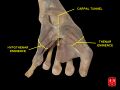

Superficial to the carpal tunnel and the flexor retinaculum, the ulnar artery and ulnar nerve pass through the ulnar tunnel/Guyon's canal.[4]

Ten structures pass through the carpal tunnel, most of them flexor tendons[2] (not the muscles themselves):

- flexor digitorum profundus (four tendons)

- flexor digitorum superficialis (four tendons)

- flexor pollicis longus (one tendon)

- Median nerve between tendons of flexor digitorum profundus and flexor digitorum superficialis

The flexor carpi radialis (one tendon) is often incorrectly stated to travel within the carpal tunnel. More precisely, it travels within the fibers of the flexor retinaculum which forms the roof of the carpal tunnel, rather than running inside the tunnel itself.